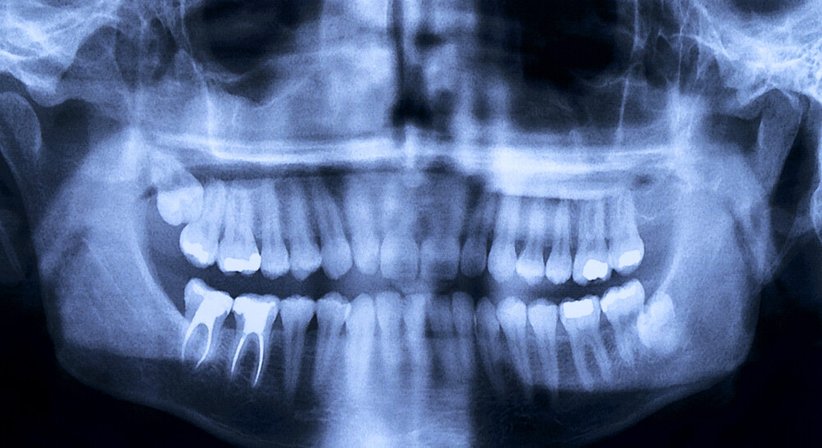

Eine ausreichende Knochenmenge und die Qualität des Knochens spielen für das erfolgreiche Einsetzen eines Zahnimplantates eine zentrale Rolle. Deshalb muss vor Implantatsetzung die Beschaffenheit des Kieferknochens mittels digitaler Volumentomografie (DVT) genau geprüft werden. Die Röntgenbilder liefern eine exakte Aussage über Knochendichte, Knochenvolumen und wichtige anatomische Strukturen.

Ist nicht genügend Knochensubstanz vorhanden, d.h. weist der Knochen nicht die erforderliche Breite, Höhe oder Dichte für die stabile und sichere Verankerung bzw. den Halt des Implantates auf, muss vor Implantation ein Knochenaufbau (in der medizinischen Fachsprache auch als Augmentation bezeichnet) durchgeführt werden.